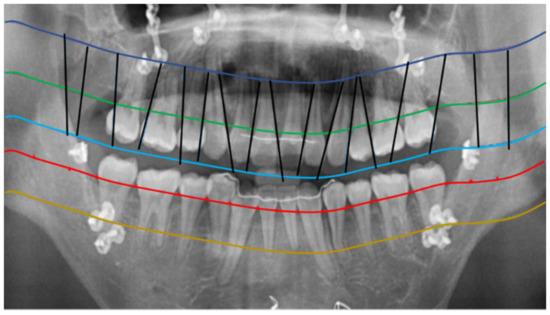

2.2.1. Curve of the Mouth

2.2.2. Curve Adjustment

2.2.3. Positioning Numbers

3. Results